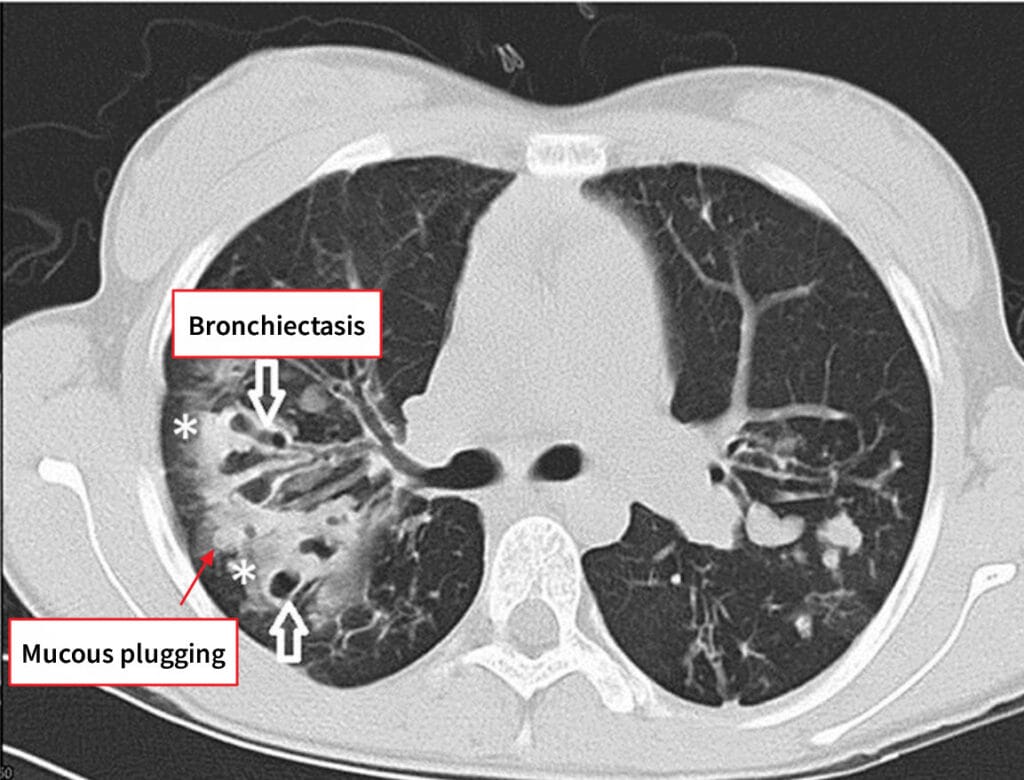

진단

– HRCT에서 기관지 직경이 인접 혈관보다 큰 ‘ring sign’, 벽 비후 확인

– 객담배양으로 세균 확인; 폐기능검사에서 가역적 또는 비가역적 기류제한